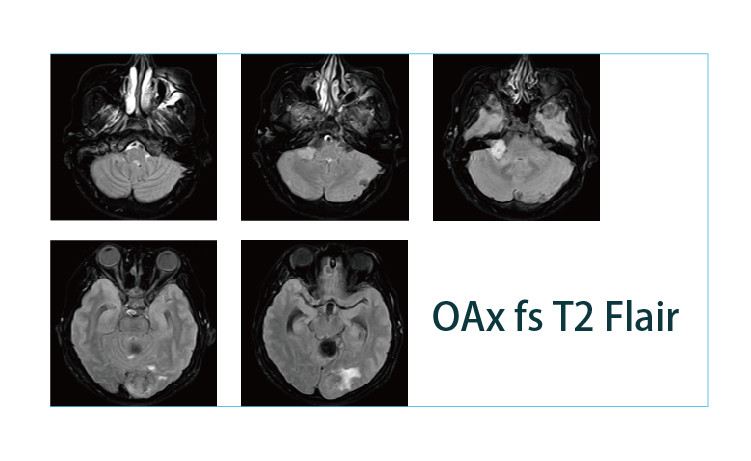

【朗润影像档案】磁共振影像病例分享(编号20190412)

2019-04-25 17:22:57